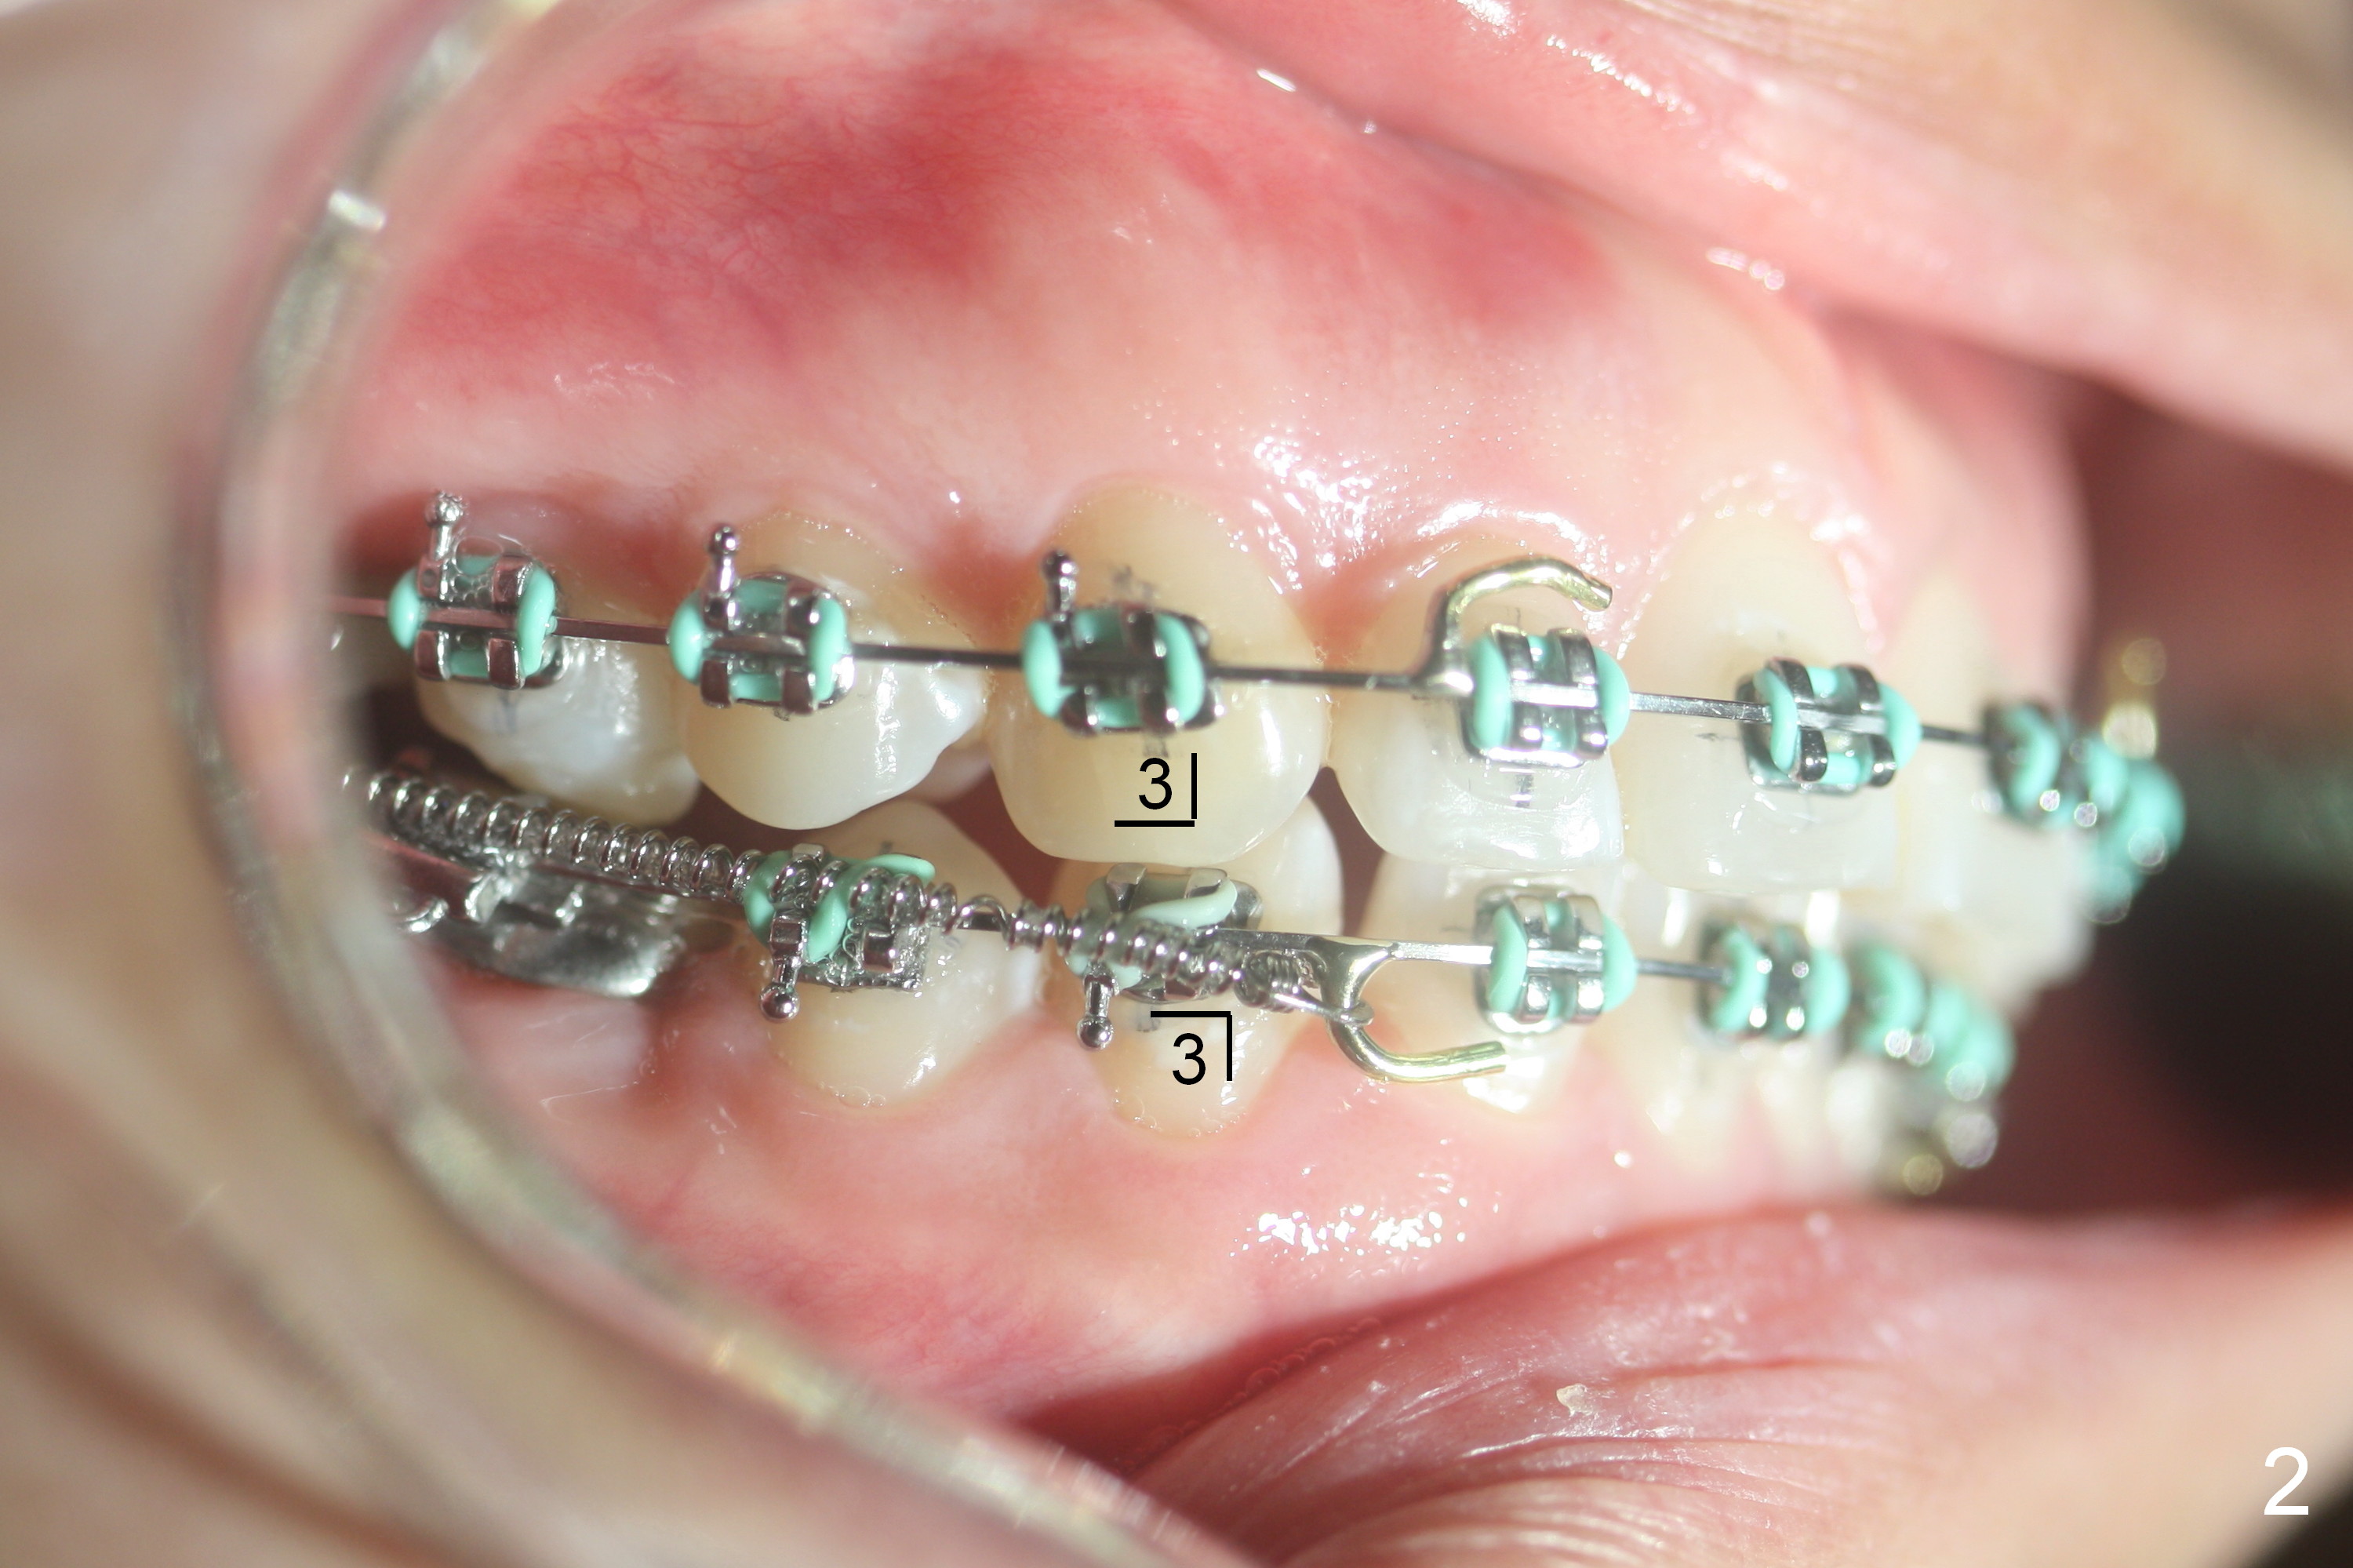

Preparation for Zygomatic Mini-implant Placement to Correct Class II Malocclusion (Fig.1,2)

5. White Ortho box: closed coil springs, Crimpable Power Hooks (right and left, Fig.3 <), crimping forceps